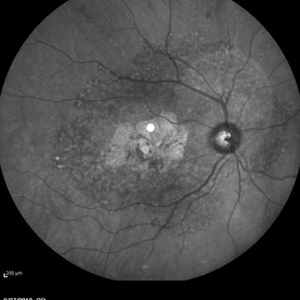

Choroidal Osteoma  + CNV Choroidal Osteoma  + CNVMar 13 2013 by Hamid Ahmadieh, MD Color fundus photograph the right eye of a 13-year-old girl with decreased VA due to CNV secondary to choroidal osteoma. Photographer: Naghmeh Nozhat, Negah Eye Center, Tehran Imaging device: Topcon Condition/keywords: choroidal neovascularization (CNV), choroidal osteoma